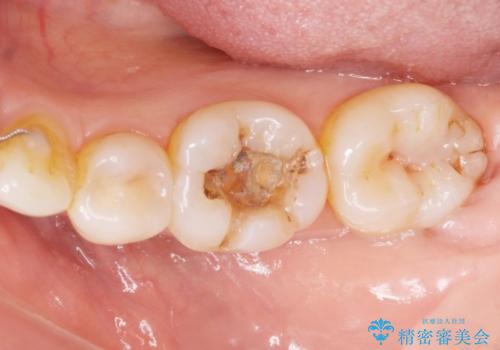

プラスチックの樹脂(CR)の治療は保険適応で白くて一日で

治療が終わるため安価であり、患者様の負担が少ない治療ですが

プラスチック樹脂は経年劣化して茶色くなります。

また耐久性もジルコニアクラウンに比べて低く、割れてしまうことがあります。